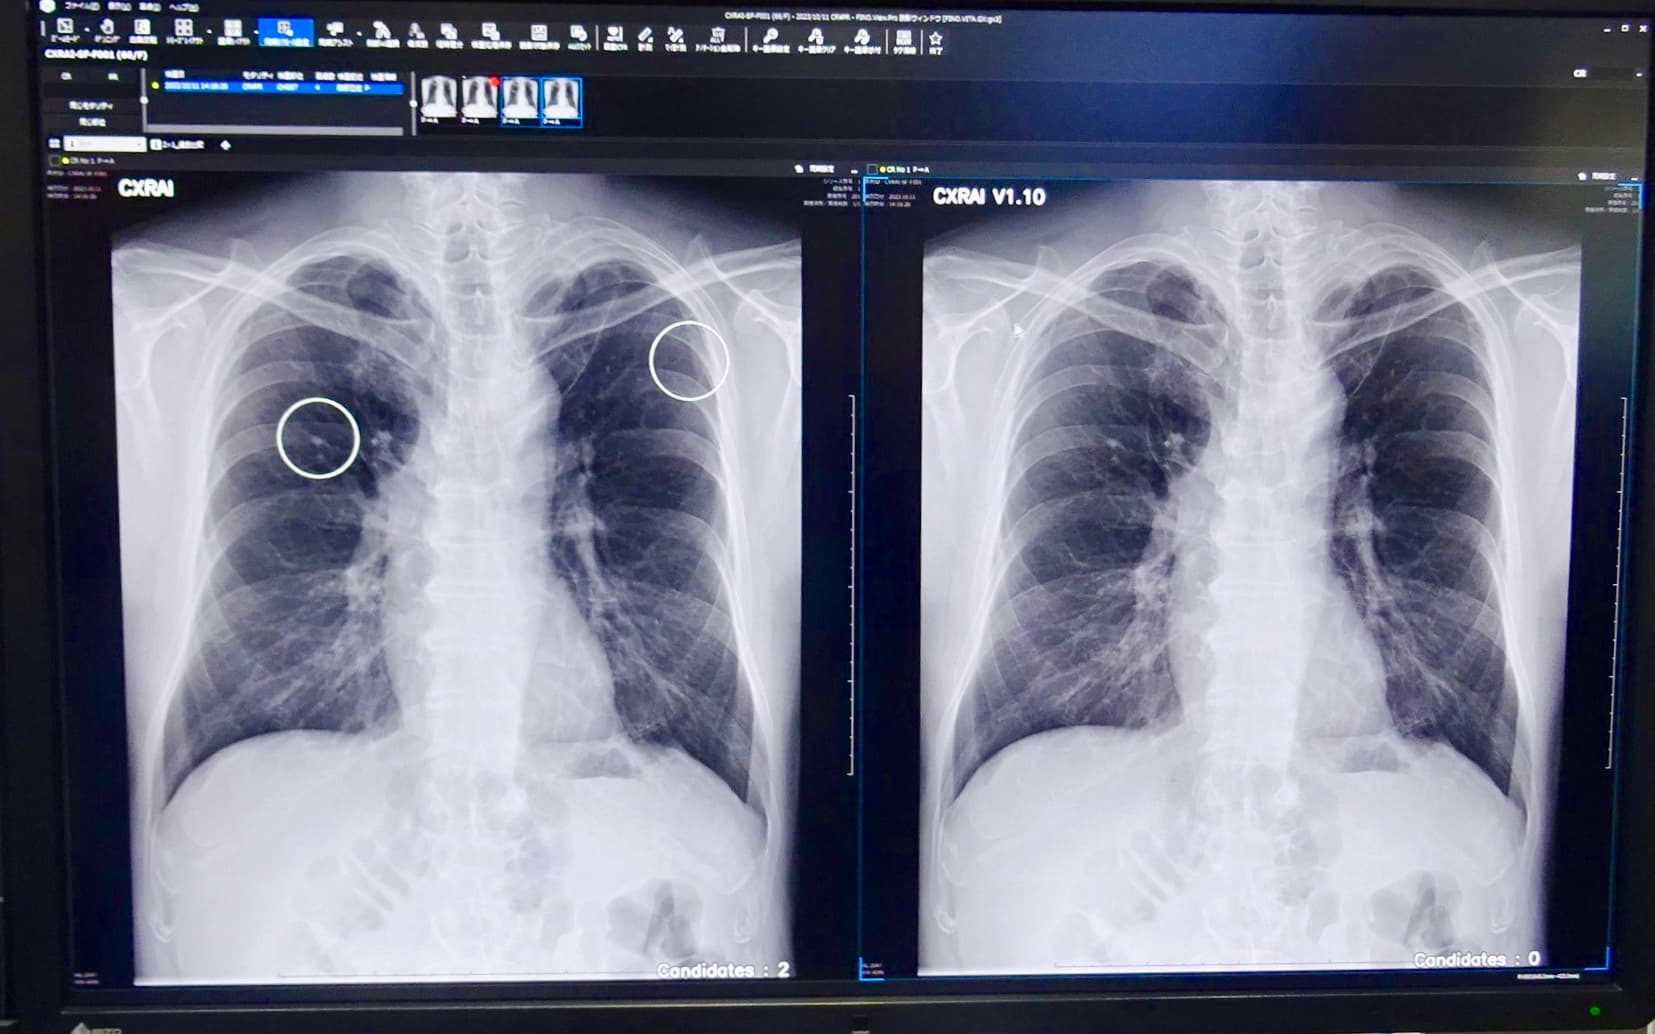

FINO.VITA.GXは胸部X画像診断支援AI「CXR Finding-i」と連携が可能。正常例に対して新バージョンで特異度が向上した症例。